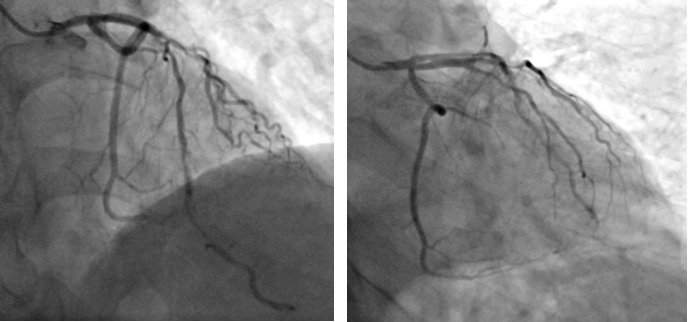

术前造影

患者为一名67岁的男性,于一月前因“反复活动后胸痛5年”入院,于右冠脉植入支架一枚。术后患者活动后胸痛较前未见明显缓解。11月9日患者返院,心血管内科二病区根据病人情况,再次为患者行PCI治疗。术中因尝试使用“预扩张球囊”于病变处扩张后效果差,但再次使用“切割球囊”于病变处切割后依旧可见钙化斑块难以充分扩张。通过血管内超声(IVUS)可见左前降最小管腔面积仅1.8mm2,深层大于270°环形钙化斑。

切割扩张后